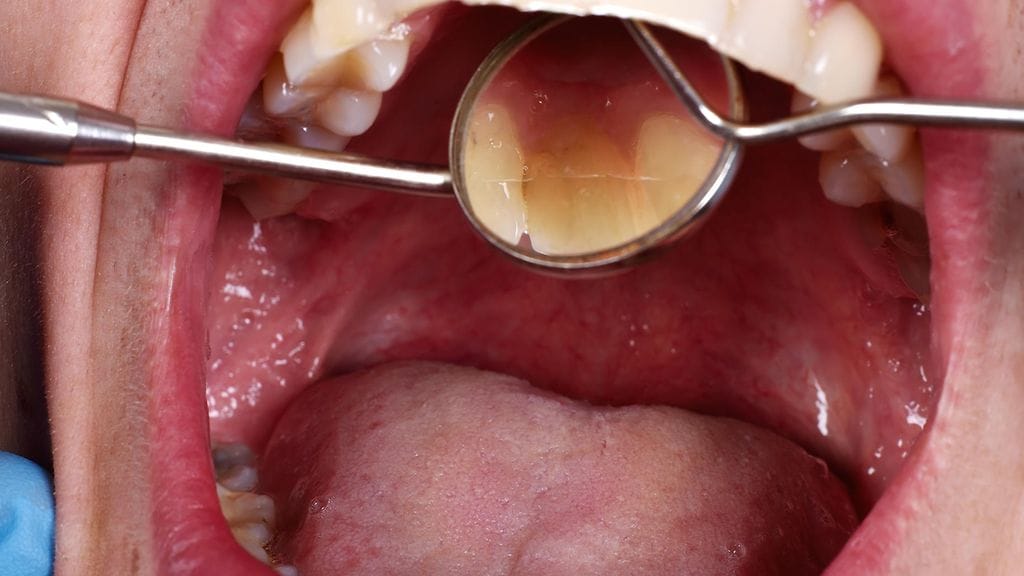

Suusyövän hälytysmerkki on selittämätön haavauma, joka ei parane parissa viikossa. Taudin voi havaita helposti esimerkiksi hammaslääkärin vastaanotolla. Jos diagnoosi tehtäisiin aikaisin, suusyöpään kuolisi paljon nykyistä vähemmän ihmisiä.

Suusyöväksi luetaan kielessä, poskien limakalvoilla, suulaessa, suupohjassa, ikenissä ja huulissa esiintyvät syövät. Valtaosassa tapauksista ensimmäinen oire on kivuton haavauma.